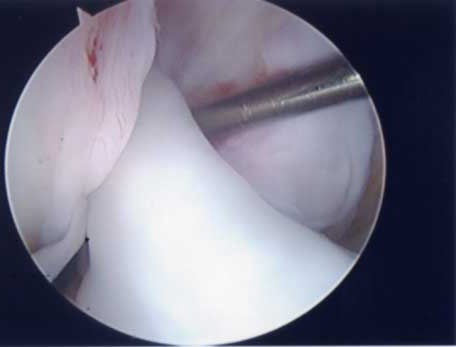

第1段階軟骨形成術

軟骨障害は最初亀裂または剥離で始まります。この状態が第一段階軟骨障害です。このことはあまり一般に知られていません。この最初の亀裂や剥離状態のうちに対処することが最も結果が良好となります。亀裂や剥離が進んでしまうと②の状態になります。

第2段階軟骨形成術

軟骨の剥離や亀裂が①より少し進んだ段階です。放っておくとさらに軟骨欠損が進み軟骨障害は広くなり且つ深くなります。この段階ではまだドリリングなどの操作は不要です。第3段階軟骨障害との間は幅広く関節鏡で見てみないと最終的に判断できません。この段階では手術結果は比較的よく平均75~90点ほどになります。

第3段階軟骨形成術

第2段階からさらに進行するとより広範囲の軟骨障害になりさらに軟骨の障害も深くなります。この段階ではドリリング手術を加えることが多くなります。第3段階ではまだ人工関節は適応はありませんのでできるだけ軟骨形成術をして膝の痛みを軽減し少しでも長く自分の膝で歩けるようにが目的です。本手術の結果は平均60~80点で患者の満足度は比較的高いので手術は安心下さい。